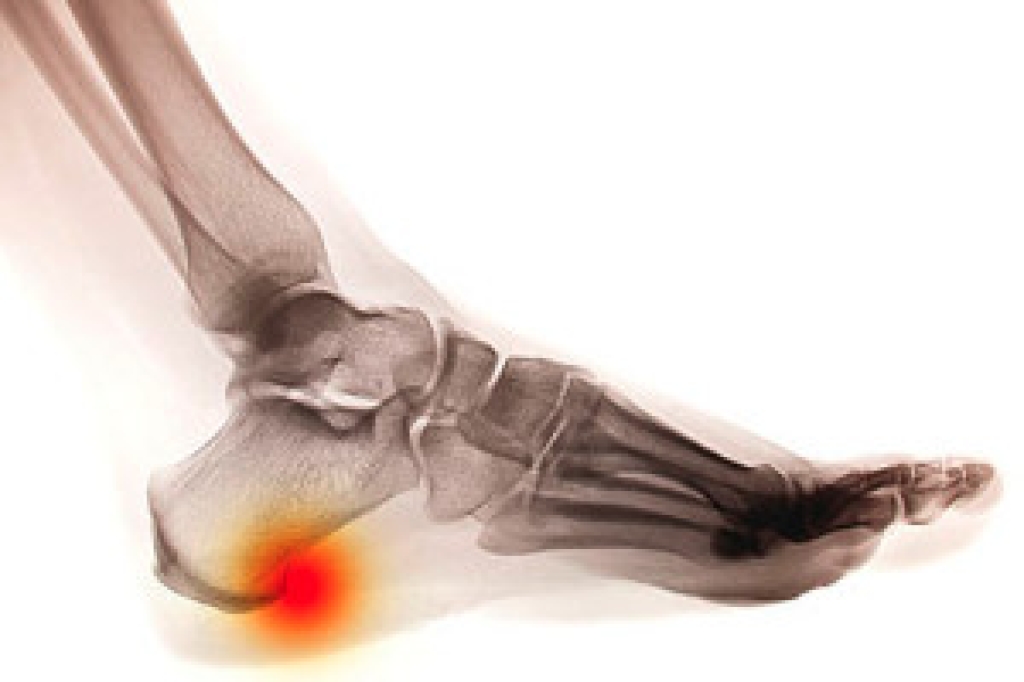

The common symptoms many people experience with arthritis can include stiffness, pain, and swelling, and it can be difficult to move the affected joint. The word arthritis means joint inflammation, and it generally causes severe pain and discomfort. The most common form of this ailment is known as osteoarthritis, and it affects millions of people in the United States. There are specific exercises that can be performed which may help to relieve some of the pain. Rheumatoid arthritis can be disabling, and it is the most common type of autoimmune arthritis. Women are more prone to get this type of arthritis, and research has indicated it may be related to hormonal changes. Gout affects the joints in the big toe, and can cause debilitating pain. Some patients find it is impossible to have anything touch the toe, and relief is often needed immediately. It happens as a result of uric acid crystals that form in the joints of the toe, and can occur from genetic factors or from eating foods that have high levels of purines. If you have arthritis in your feet, it is suggested you confer with a podiatrist who can guide you toward correct treatment options.

If you suspect your arthritis is affecting your feet, it is crucial that you see a podiatrist immediately. Your doctor will be able to address your specific case and help you decide which treatment method is best for you.